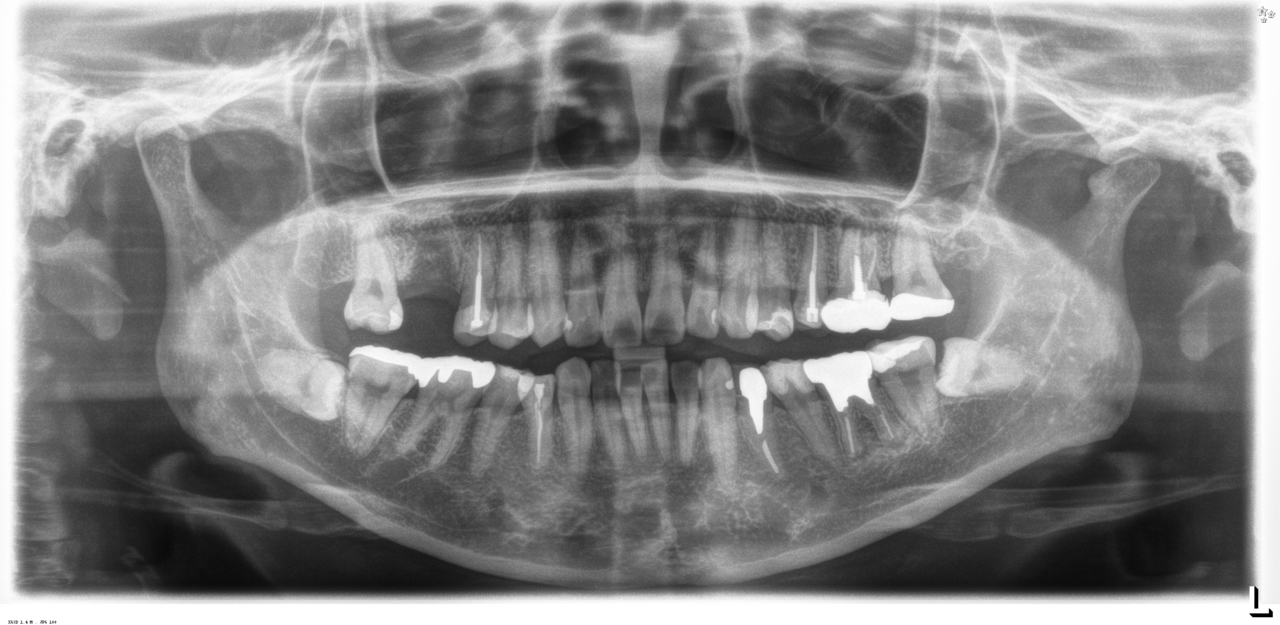

治療前

下の歯は歯周病でグラグラです。

後のインプラント手術時に、抜歯します。

CT撮影

埋入位置を決めるための装置(ラジオグラフィックガイド)を口腔内に入れCTを撮影します。

完成後のレントゲン写真

最終的な被せ物を装着した状態のレントゲン写真。

(今回は下顎ですが、その前に上顎は治療済みです。)

レントゲンを撮影します。

ここでは、むし歯・歯周病・嚢胞・腫瘍の有無や状態、顎関節異常、顎骨の状態、親知らずの有無と生え方、埋伏歯の有無などを確認します。